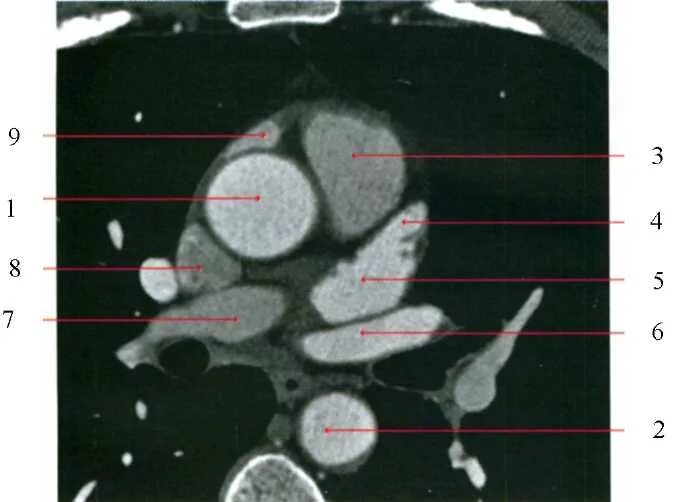

Легочный ствол на кт